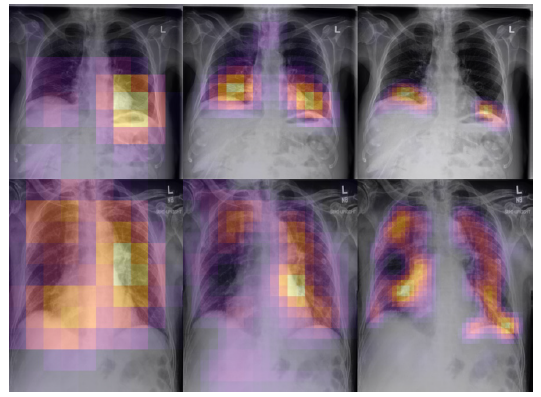

- As an additional benefit, architectures that truncate pooling layers will also produce higher-resolution class activation maps by Grad-CAM.

- The higher-resolution class activation maps (CAMs) may more effectively localize pathologies with little to no decrease in classification performance. In clinical settings, improved explainability through better CAMs may be useful for validating predictions and diagnosing mispredictions.